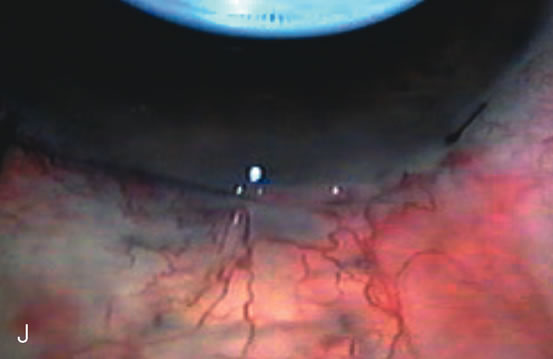

Fig. 5. Anterior chamber angle changes associated with lens extraction and PCIOL This 65-year-old Vietnamese woman has a long-standing history of chronic angle-closure glaucoma treated with laser peripheral iridectomy. The optic nerve demonstrated mild glaucomatous damage and IOP was moderately controlled on two antiglaucoma medications. The cataract was removed through temporal clear corneal phacoemulsification with foldable acrylic IOL. A. Symptomatic cataract in narrow-angle glaucoma eye with patent iridectomy. B. Intraoperative goniophotograph showing crowding of angle with increasing narrowness due to phacomorphic component. C. Intraoperative photograph showing temporal clear corneal approach with IOL in the capsular bag. D. Intraoperative goniophotograph demonstrating deepening of chamber angle following lens extraction. Proposed theories for IOP reduction following lens extraction with complete wound closure:

1. Anterior chamber deepening with improved access to trabecular meshwork

2. Increase in traction on the trabecular meshwork

3. Improved outflow facility mediated by an increase in prostaglandin release

4. Reduction in aqueous humor production

5. Atrophy of ciliary body processes

6. Goniosynechialysis due to intraoperative over deepening of AC with viscoelastic

7. Relief of undiagnosed pupil block